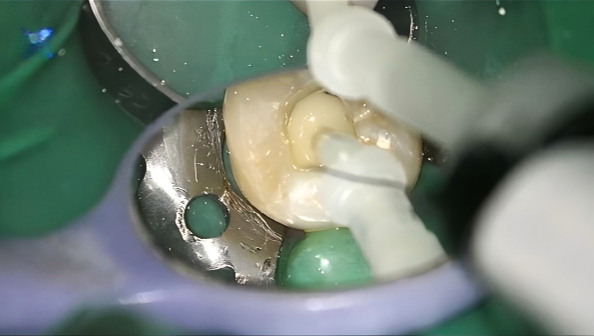

1. Isolation and Access Refinement

Rubber dam isolation was applied for moisture control. The access cavity was cleaned to remove residual debris and expose sound dentin surfaces for adhesive procedures.

4. Core Build-Up

A dual-cure core build-up material UltraCore (HUGE) was injected and shaped anatomically. The dual-curing mechanism ensured complete polymerization throughout the core.

5. Finishing and Final Appearance

Core material was fully cured and then refined to re-establish proper anatomical contours. The restored surface showed smooth integration with the surrounding tooth structure, and the overall appearance was natural and consistent with adjacent dentition.